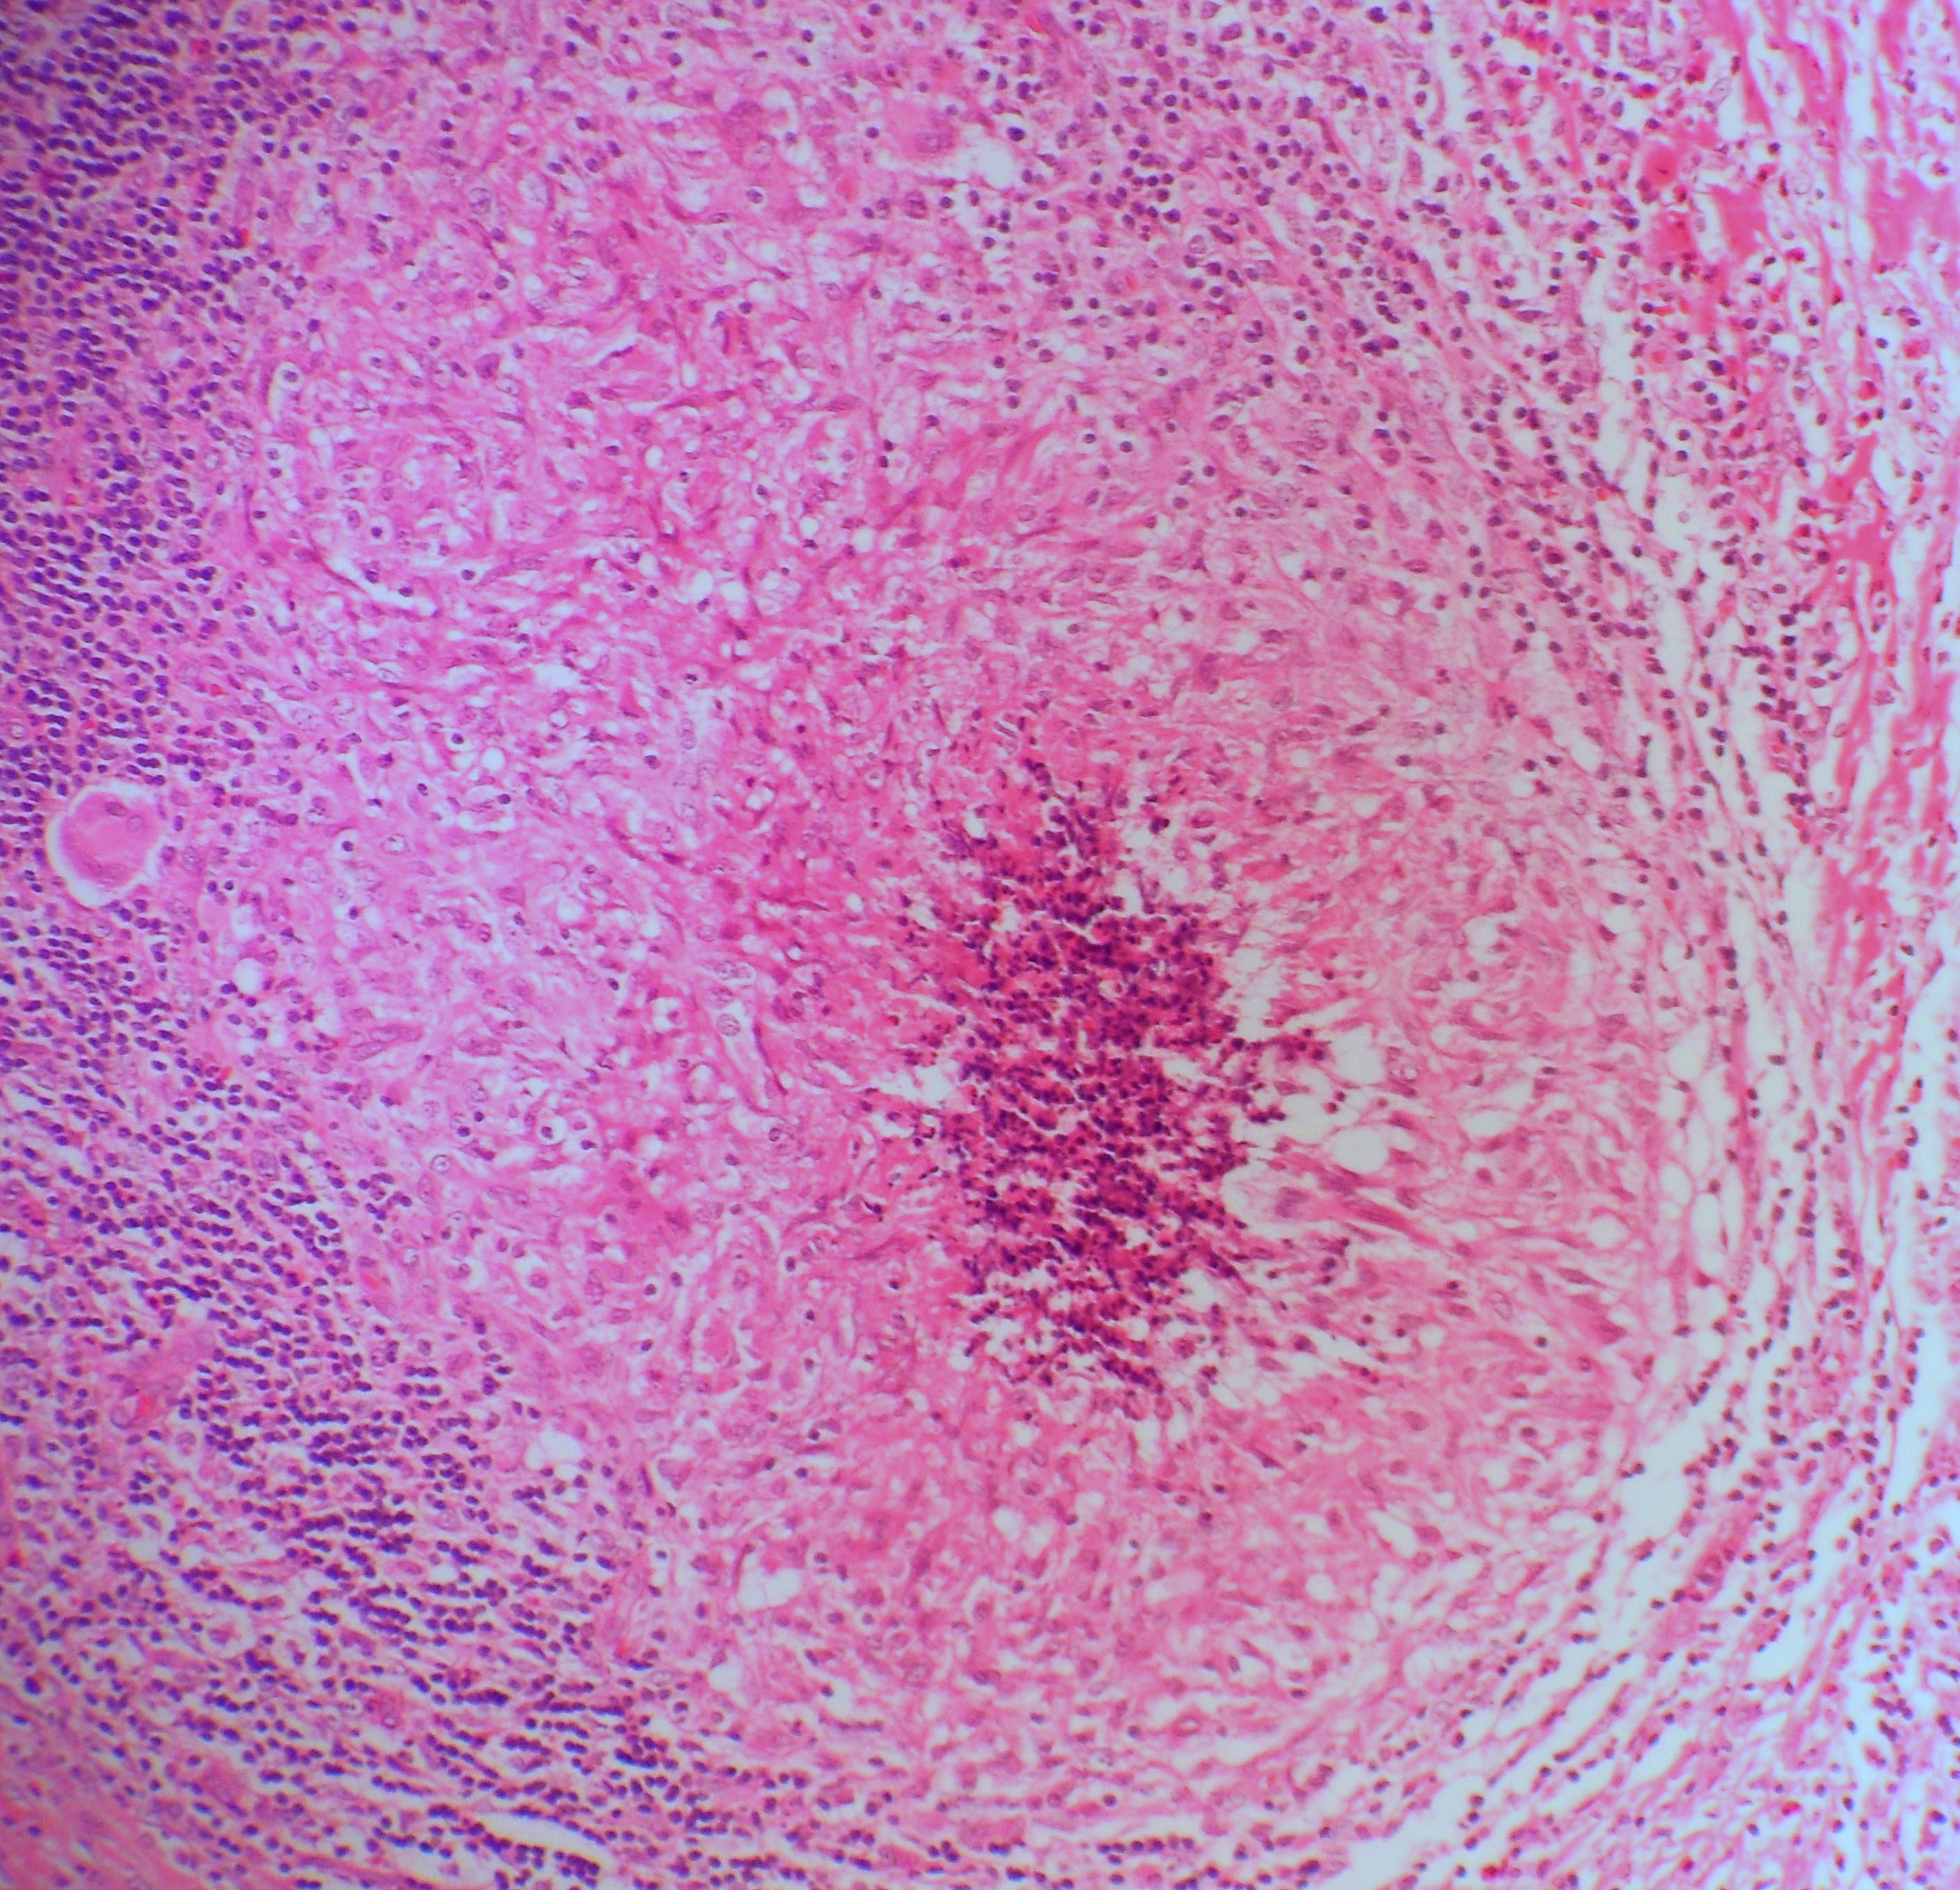

Как прогрессирует саркоидоз: что происходит на тканевом уровне

На тканевом или клеточном уровне прогрессирование болезни саркоидоза можно разделить на три фазы:

- Первое видимое изменение — воспаление.

- На второй стадии формируются гранулемы. Гранулемы представляют собой образования или узелки в хронически воспаленной ткани и являются классическим признаком саркоидоза. Гранулемы — это попытка организма отгородить или изолировать организмы и другие инородные частицы, которые иммунной системе трудно уничтожить или избавиться от них.

- В третьей фазе происходит фиброз (рубцевание) тканей или органов. Если рубцы обширны в жизненно важном органе, саркоидоз иногда приводит к летальному исходу.

У некоторых людей болезнь переходит от одной фазы к другой в тканях пораженного органа.В других случаях разные фазы тканевых изменений происходят в одном и том же органе одновременно. У многих пациентов с саркоидозом гранулемы проходят сами по себе через 2–3 года, при этом пациент ничего не знает и ничего не предпринимает. В других случаях гранулемы прогрессируют до необратимого фиброза. Изменения иммунной системы, которые позволяют заболеванию одного человека прогрессировать, в то время как болезнь другого человека проходит, недостаточно изучены и продолжают изучаться.

Альвеолит либо проходит сам по себе, либо прогрессирует до образования гранулемы. Образцы легочной ткани могут показать наличие гранулем.

Гранулемы в легких могут привести к сужению дыхательных путей, увеличению лимфатических узлов в грудной клетке, а также к воспалению и рубцеванию (фиброзу) легочной ткани.Рубцевание приводит к тому, что легочная ткань становится жесткой и разрушает воздушные мешочки, затрудняя дыхание.